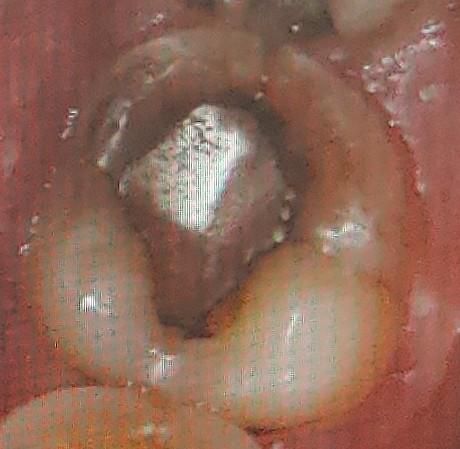

• 1번 째 사진

• 2번 째 사진

사진상으로도 치아 뒷부분 치아에 금이 간게 보입니다. 계속해서 씹을 때아프거나 불편하다면 치과에 가셔서 검진후 치료를 받으셔야될것같습니다.

아말감을 떼웠을 당시에도 충치가 얕지는 않았습니다. 충치, 크랙 둘다 가능성이 있을 것 같습니다. 치아 상태가 원래 안 좋은 와중에 딱딱하거나 질긴 음식으로 자극이 가해져서 그렇습니다.